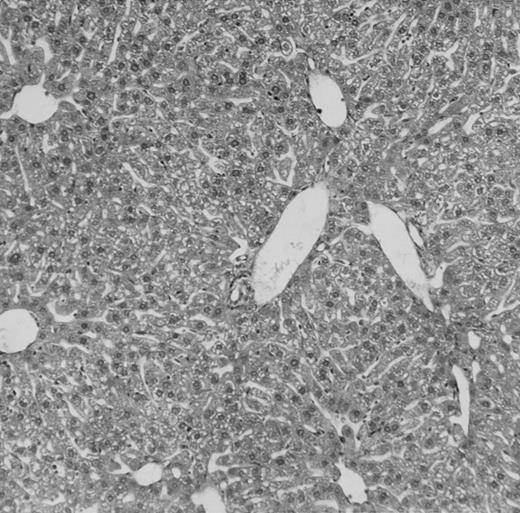

Histologic findings. Organs were collected at different times after BMT and tissue sections were stained with hematoxylin and eosin. Original magnifications for spleen (left) and liver (right) are ×40 and ×100, respectively. (A) B6 mice receiving FVB BM plus EpTK T cells. (B) Control group receiving BM only.

(C) B6 mice receiving FVB BM plus EpΔTK T cells and treated with GCV. (D) B6 mice receiving FVB BM plus EpΔTK T cells, treated with GCV, and developing a late onset GVHD (day 54).

FVB BM-grafted B6 mice: a model of lethal GVHD.We developed a model of GVHD resulting in 100% mortality soon after BMT using FVB mice, a strain not previously used as BM donors in experimental allogeneic BMT. We tested different combinations of recipient irradiation doses, as well as injected BM cell and CD3+ peripheral T-cell numbers. When 10-Gy–irradiated B6 mice were reconstituted with 107 FVB BM cells, we observed prolonged survival, whereas all ungrafted animals died before day 16 (Fig 2). In these conditions, more than 98% of splenocytes were of donor origin (Fig 3A). When 107 CD3+ peripheral T cells from mice of FVB genetic background were added to the FVB BMT, all animals died of GVHD between days 7 and 34 (Fig 2). Similar results were obtained using either PBS-treated mice receiving EpTK or EpΔTK peripheral T cells or GCV-treated mice receiving FVB nontransgenic peripheral T cells. Notably, this observation also indicates that both TK- and ΔTK-expressing T cells in the absence of GCV are fully competent to induce a lethal GVHD. Histopathologic examination of spleen and liver of these animals showed characteristic GVHD lesions such as (1) architecture disruption, necrosis, and congestion in the spleen; (2) hepatic periportal necrosis; (3) mononuclear portal infiltrates; and (4) endothelialitis of portal or centrolobular veinules (Fig 4A). By comparison, B6 mice receiving only FVB BM had a normal histology (Fig 4B).

Protection from GVHD was slightly less efficient in the group receiving EpΔTK CD3+ T cells. The survival rate was 79% at day 60 and 67% at day 120 (Fig 2B). However, two different outcomes must be distinguished. On the one hand, a majority of mice behaved as GCV-treated animals receiving EpTK T cells. They were apparently healthy, presented no skin lesions during a 120-day observation period, and showed complete donor-type hematologic reconstitution. There were no histological signs of GVHD in the spleen or liver (Fig 4C).